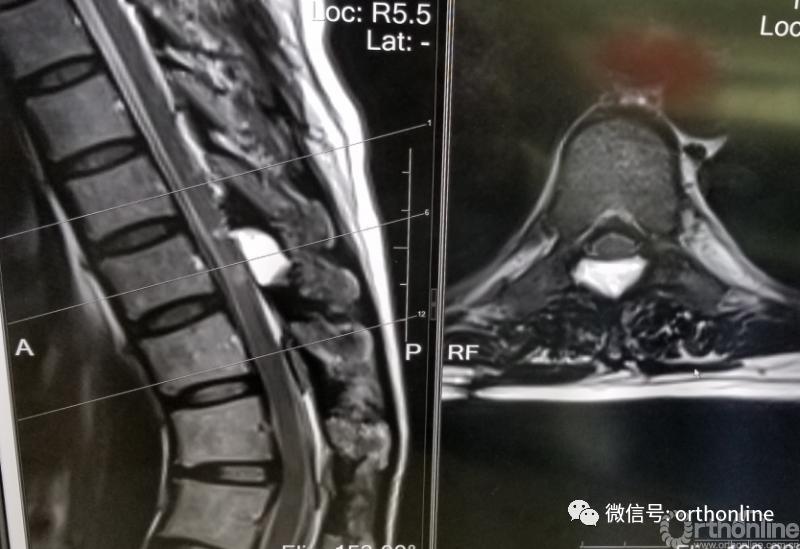

脊柱内镜手术通常作为首选手术方法,能有效地减压并进行相应的处理。适用于胸椎管狭窄症,如胸椎黄韧带肥厚症、胸椎间盘突出症、胸椎后纵韧带骨化症等,尤其适合单节段狭窄者。

局限性脑脊液漏

硬膜囊骨化与黄韧带钙化粘连一体时,为了减压充分和硬膜囊钙化形成的硬壳需要部分切除,会造成术后脑脊液漏的发生。内镜下可使用人工硬脊膜或者明胶海绵填塞至椎板层面,将脑脊液漏封堵于椎管层面,避免形成窦道。不建议术后放置引流管。